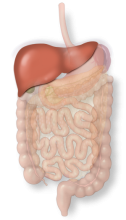

The liver is a solid organ that produces bile for fat digestion and is also the first stop for the majority of absorbed nutrients.